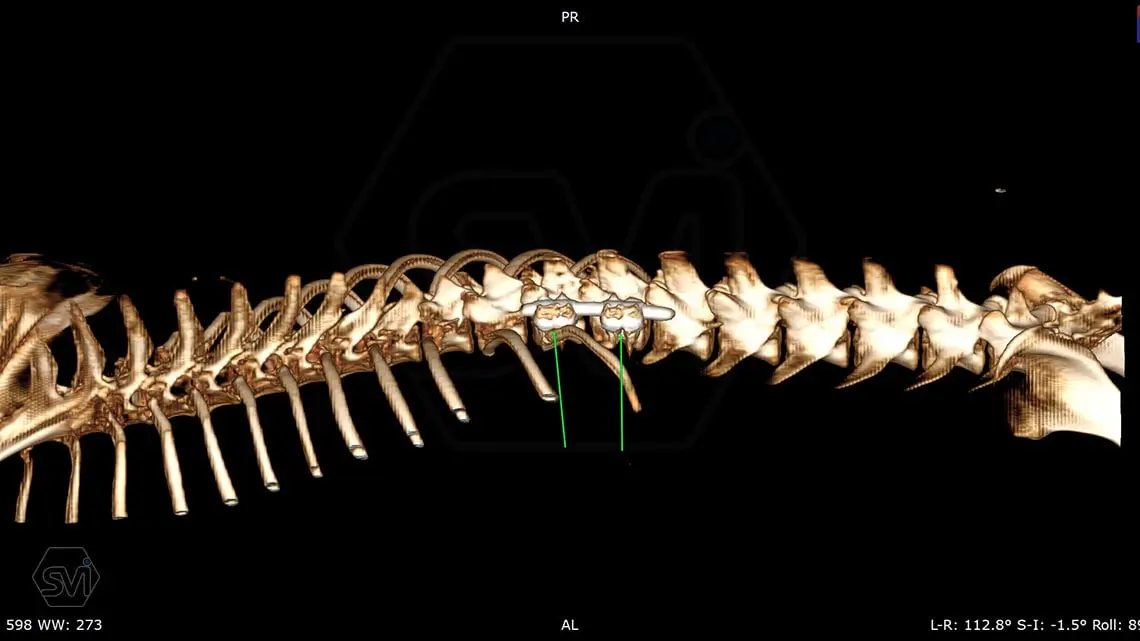

L6 vertebral body fracture fixation with 2.7-mm SOP-LC system